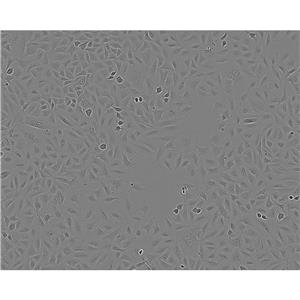

"MNNG/HOS Cells人骨肉瘤细胞系(提供STR图谱)

" "传代比例:1:2-1:4(首次传代建议1:2)

" "背景信息:骨肉瘤;女性

" "换液周期:每周2-3次

" "生长特性:贴壁

" "MNNG/HOS Cells人骨肉瘤细胞系(提供STR图谱)

" "形态特性:详见细胞说明书

" "MNNG/HOS Cells人骨肉瘤细胞系(提供STR图谱)

" "MNNG/HOS Cells人骨肉瘤细胞系